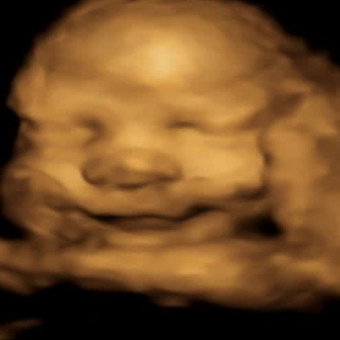

Baby Boy Biese

Katie & Nicole Biese

January 21, 2026

Welcome to our registry! We are so excited to grow our family and cannot wait to meet our little baby boy. Here is a list of some stuff we need, any help is greatly appreciated!